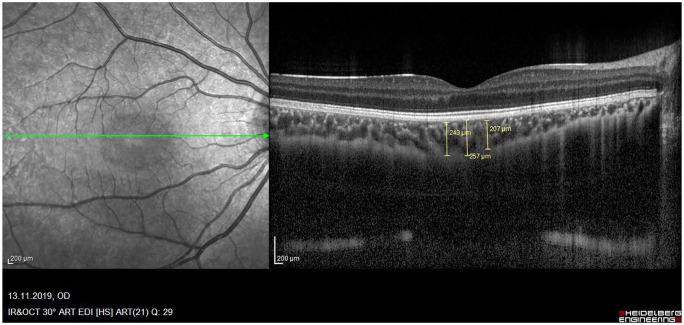

To evaluate inner plexiform layer (IPL), ganglion cell layer (GCL), and retinal nerve fiber layer (RNFL) thicknesses, as well as the relationship between choroidal thickness (CT) and ocular pulse amplitude (OPA) in type 1 diabetic children without diabetic retinopathy (DR).

Group 1 ( = 44) consisted of pediatric patients with type 1 DM without DR, and Group 2 ( = 65) of pediatric control subjects. Both intraocular pressure (IOP) and OPA were measured using a dynamic contour tonometer. CT, IPL, GCL, and RNFL were all measured using spectral domain optical coherence tomography (OCT).

The mean IOP and OPA values were 16.67 ± 2.34 and 1.85 ± 0.34, respectively, in group 1, and 15.14 ± 2.17 and 1.65 ± 0.25 in Group 2 ( = 0.001 for both). The mean subfoveal CT value was 294.30 ± 67.61 μm in group 1 and 394.42 ± 69.65 μm in Group 2 ( < 0.001). The mean GCL and RNFL values were 1.09 ± 0.11 and 96.46 ± 11.69, respectively, in group 1, and 1.14 ± 0.09 and 101.73 ± 9.33 in Group 2 ( = 0.005 and  = 0.008, respectively).

IOP and OPA values were higher, and CT, GCL, and RNFL values were lower in children with type 1 DM during the early stages than in the healthy control group. These findings suggest that CT may be a marker of retinal involvement in children with type 1 DM without DR.

评估1型糖尿病且无糖尿病视网膜病变(DR)患儿的内网状层(IPL)、神经节细胞层(GCL)和视网膜神经纤维层(RNFL)厚度,以及脉络膜厚度(CT)与眼脉搏振幅(OPA)之间的关系。

第1组(n = 44)由1型DM且无DR的患儿组成,第2组(n = 65)为儿科对照受试者。使用动态轮廓眼压计测量眼压(IOP)和OPA。使用光谱域光学相干断层扫描(OCT)测量CT、IPL、GCL和RNFL。

第1组的平均IOP和OPA值分别为16.67±2.34和1.85±0.34,第2组为15.14±2.17和1.65±0.25(两者P均 = 0.001)。第1组的平均黄斑下CT值为294.30±67.61μm,第2组为394.42±69.65μm(P < 0.001)。第1组的平均GCL和RNFL值分别为1.09±0.11和96.46±11.69,第2组为1.14±0.09和101.73±9.33(P分别 = 0.005和P = 0.008)。

1型DM患儿早期的IOP和OPA值较高,而CT、GCL和RNFL值低于健康对照组。这些发现表明,CT可能是1型DM且无DR患儿视网膜受累的一个标志物。